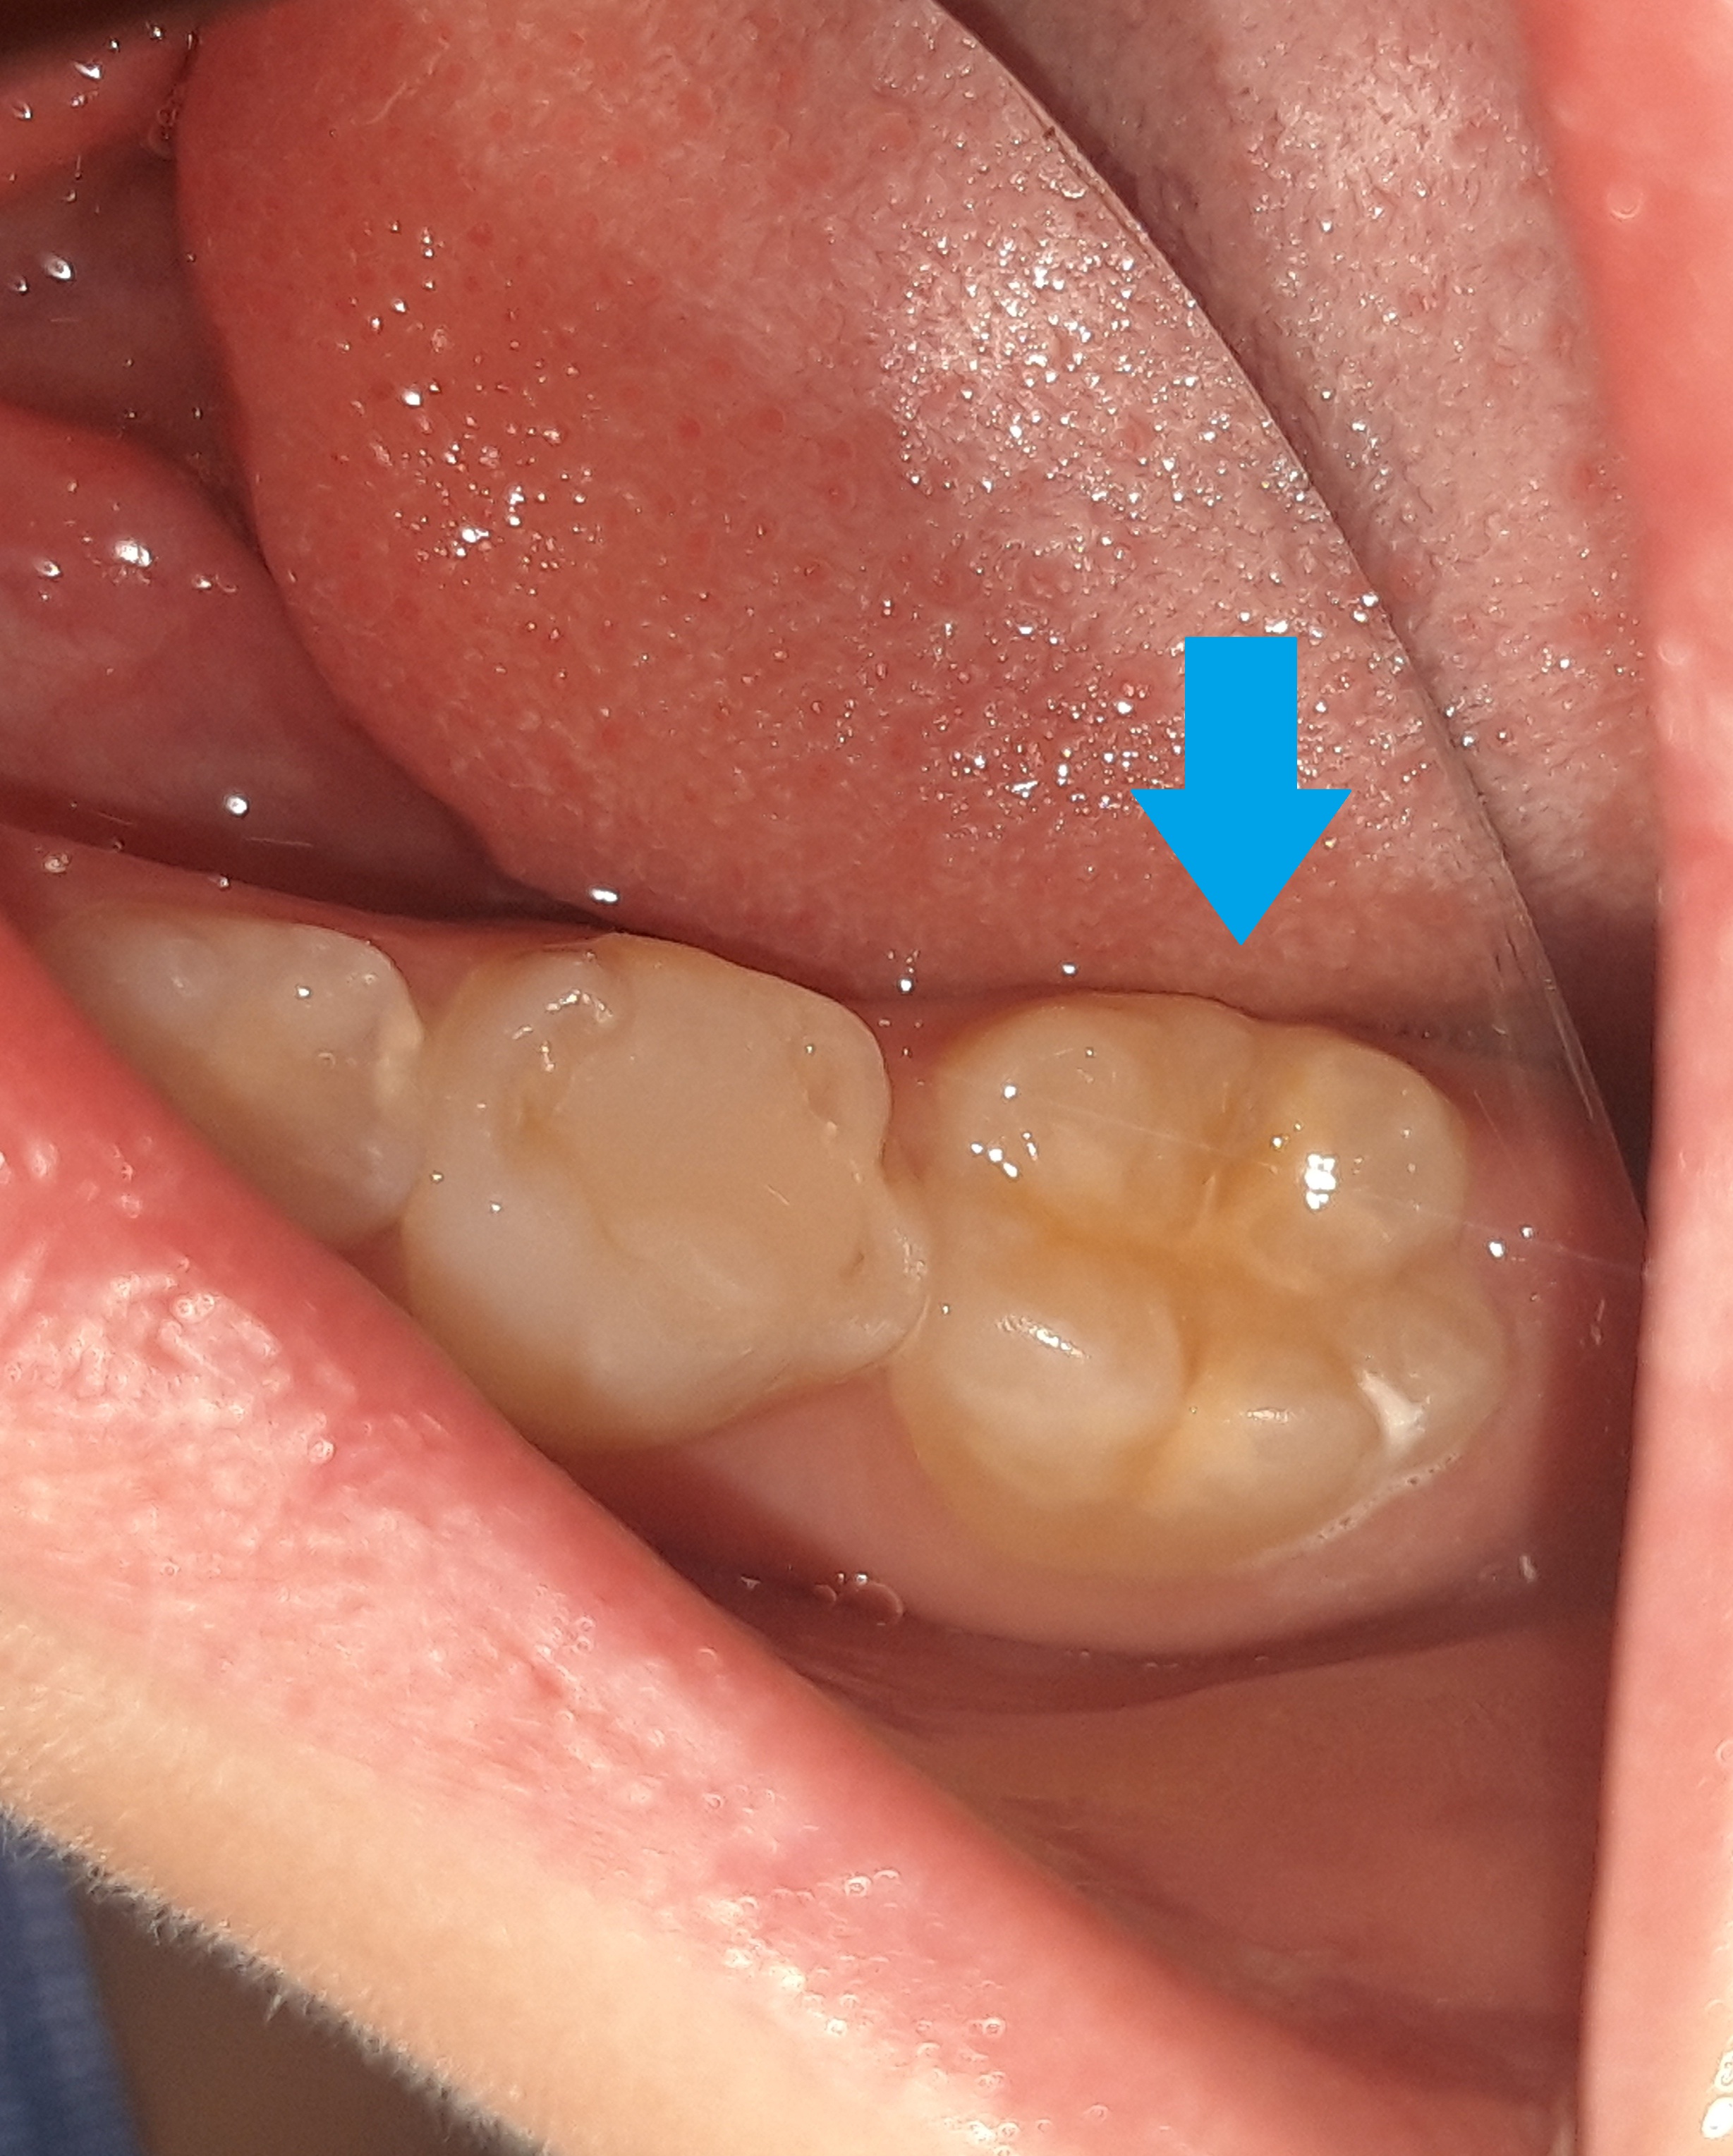

Στο αγόρι αυτό τοποθετήθηκε προληπτική κάλυψη στη μασητική επιφάνεια του μόνιμου κάτω πρώτου γομφίου, ώστε το δόντι να είναι προστατευμένο από την τερηδόνα. Η κάλυψη της μασητικής επιφάνειας ενός δοντιού με sealant μειώνει την κατακράτηση υπολειμμάτων τροφών στις σχισμές και τις αύλακες του δοντιού αυτού με αποτέλεσμα να συγκεντρώνονται και λιγότερα μικρόβια στο δόντι. Παράλληλα το παιδί μπορεί να βουρτσίζει πιο αποτελεσματικά και εύκολα τα πίσω δόντια καθώς μειώνονται οι πτυχές του δοντιού, όπου παγιδεύονται συνήθως τροφές.

Ο χρόνος ζωής ενός sealant κυμαίνεται από 2 – 5 χρόνια.